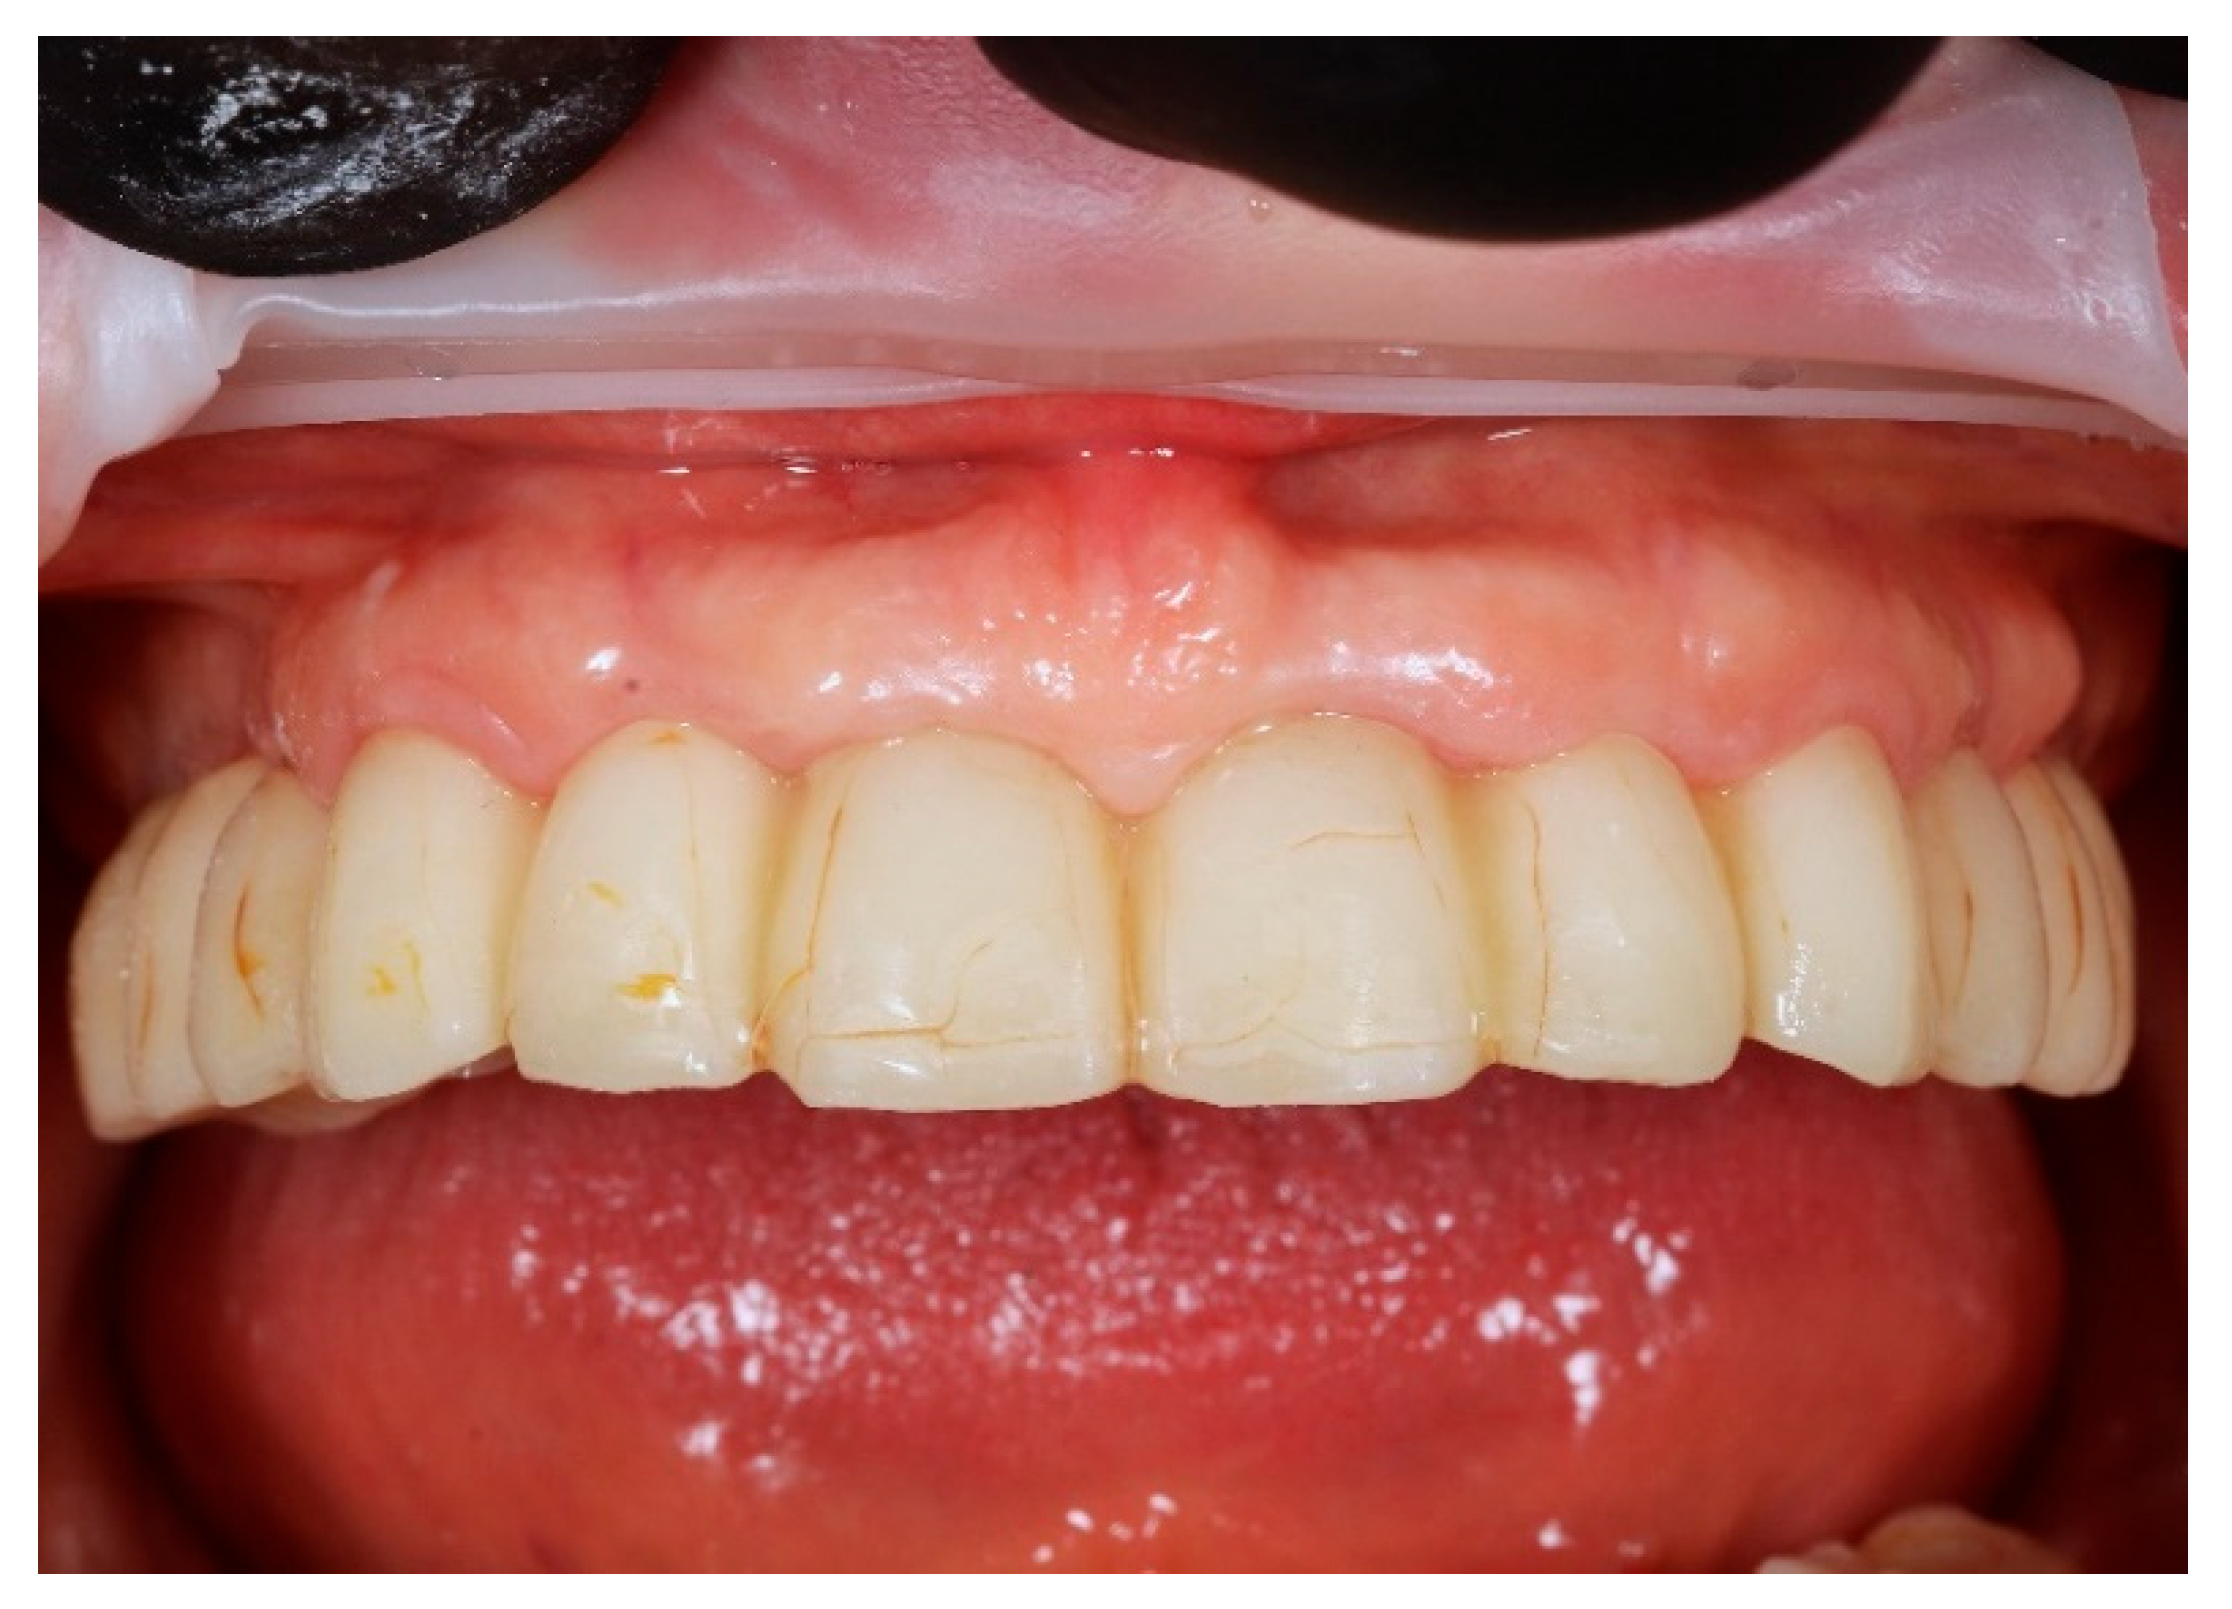

Based on the merged datasets (biocopy + SmartFlags® scan), the provisional screw-retained, implant-supported full-arch prosthesis was designed in Exocadsoftware (Exocad GmbH, Darmstadt, Germany) and subsequently fabricated using OnX Tough 2 resin (SprintRay Inc., Los Angeles, CA, USA) by means of 3D printing. The intaglio (tissue-facing) surface was polished [18], while the labial surface was characterised and glazed to improve aesthetics (Optiglaze Clear, GC International AG, Luzern, Switzerland). As demonstrated in the accompanying clinical photographs, minor superficial cracks in the glaze layer are visible on the external surface of the prosthesis (Figure 8).

Finally, the prosthesis was delivered by fixing to the multi-unit abutments with screws. Clinical adjustments were performed to ensure perfect fit, occlusion, phonetics, and aesthetics. The patient reported immediate improvement in comfort and satisfaction compared to the acrylic splint (Figure 9 and Figure 10).

Figure 8. A digitally planned, 3D-printed full-arch provisional restoration ready for assembly.